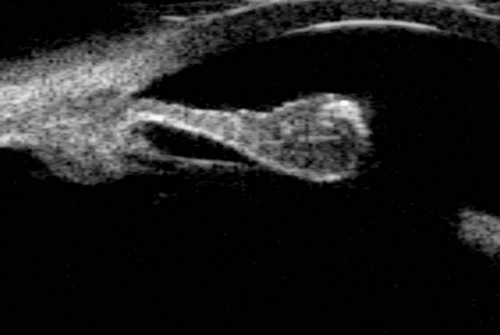

Figure 12: Blunt trauma causing cyclodialysis cleft. A direct communication between

the supra-ciliary space and anterior chamber can be visualised.

Cyclodialysis clefts

Cyclodialysis clefts can be iatrogenic or more commonly secondary to contusion injuries. Defined as a disinsertion of the ciliary body from the scleral spur, the injury allows access to the suprachoroidal space resulting in hypotony. Visualisation of the supraciliary fluid and the connection from the anterior chamber to the supraciliary space confirms the diagnosis of a cyclodialysis cleft (Figure 12). Direct gonioscopy once the eye is filled with viscoelastic is the definitive way of determining the location and extent of the cleft, principally because the iris will otherwise obscure the angle. UBM is useful in this scenario as it provides a way of knowing the location and extent of the cleft without physically entering the anterior chamber.